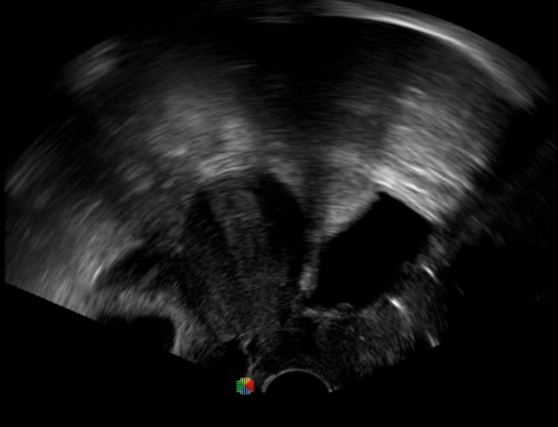

經(jīng)食道超聲 大動脈短軸

TEE(經(jīng)食道超聲心動圖)將超聲探頭置入食道內(nèi),從心臟的后方向前近距離探查其結(jié)構(gòu) ,克服了經(jīng)胸超聲檢查的局限性,避免肺內(nèi)氣體、胸壁脂肪、胸廓畸形等因素影響,觀察角度更多,圖像更加清晰,測量數(shù)據(jù)更準(zhǔn)確。